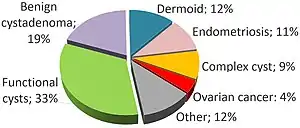

Most ovarian cysts are related to ovulation, being either follicular cysts or corpus luteum cysts.[1] Other types include cysts due to endometriosis, dermoid cysts, and cystadenomas.[1] Many small cysts occur in both ovaries in polycystic ovary syndrome (PCOS).[1] Pelvic inflammatory disease may also result in cysts.[1] Rarely, cysts may be a form of ovarian cancer.[1] Diagnosis is undertaken by pelvic examination with an ultrasound or other testing used to gather further details.[1]

Functional

Functional cysts form as a normal part of the menstrual cycle. There are several types of functional cysts:

- Follicular cyst, the most common type of ovarian cyst. In menstruating women, a follicle containing the ovum, an unfertilized egg, will rupture during ovulation. If this does not occur, a follicular cyst of more than 2.5 cm diameter may result.[4]

- Corpus luteum cysts appear after ovulation. The corpus luteum is the remnant of the follicle after the ovum has moved to the fallopian tubes. This normally degrades within 5 to 9 days. A corpus luteum that is more than 3 cm is defined as cystic.[4]

- Theca lutein cysts occur within the thecal layer of cells surrounding developing oocytes. Under the influence of excessive hCG, thecal cells may proliferate and become cystic. This is usually on both ovaries.[4]

Non-functional

Non-functional cysts may include the following:

Ovarian cysts may be classified according to whether they are a variant of the normal menstrual cycle, referred to as a functional or follicular cyst.[4]